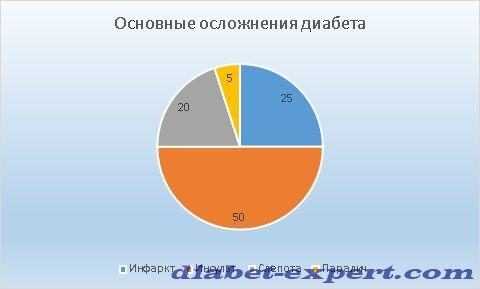

На диаграмме указано % соотношение осложнений диабета 1 типа.

Продолжительность жизни при сахарном диабете 1 типа, если диагноз был установлен в 14-15 летнем возрасте, составляет 26-36 лет. До 50 лет доживает только 10-15% больных. Прогноз для людей с заболеванием 2 типа более благоприятен. Многие больные доживают до старости.

У диабетиков 1 типа преждевременная смерть наступает в 2,5 раз чаще, чем у людей, не страдающих никакими заболеваниями. Больные с 2 типом диабета доживают до старости в 1,5 раза реже, чем здоровые люди.